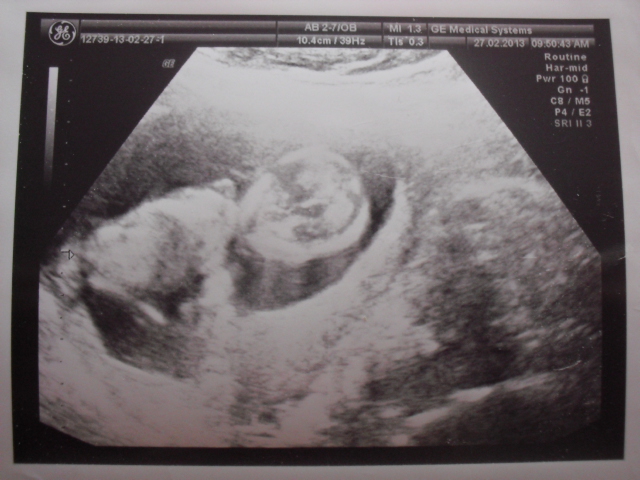

Tady Vám přikládám nějaké fotečky z UTZ, sice nejsou úplně nová, ale alespoň nějaké! Ať vidíte, jak nám maličký roste!

Jinak krany fotečky,je vidět jak hezky roste